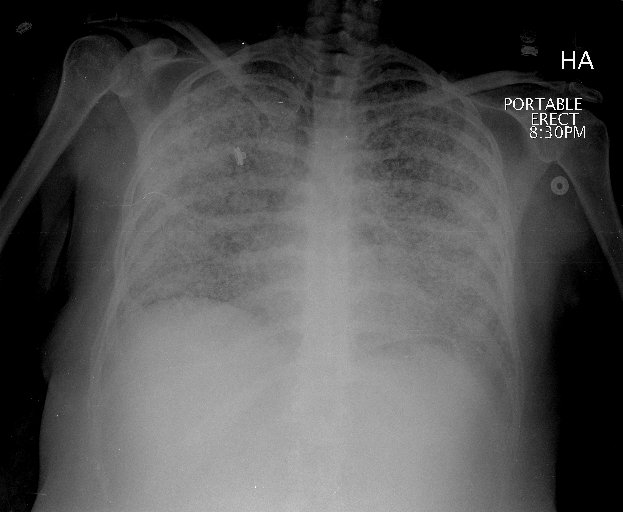

Figure 1: Posterior-anterior (PA) chest radiograph with extensive, poorly defined nodular opacities throughout both lungs and apical bullous disease.